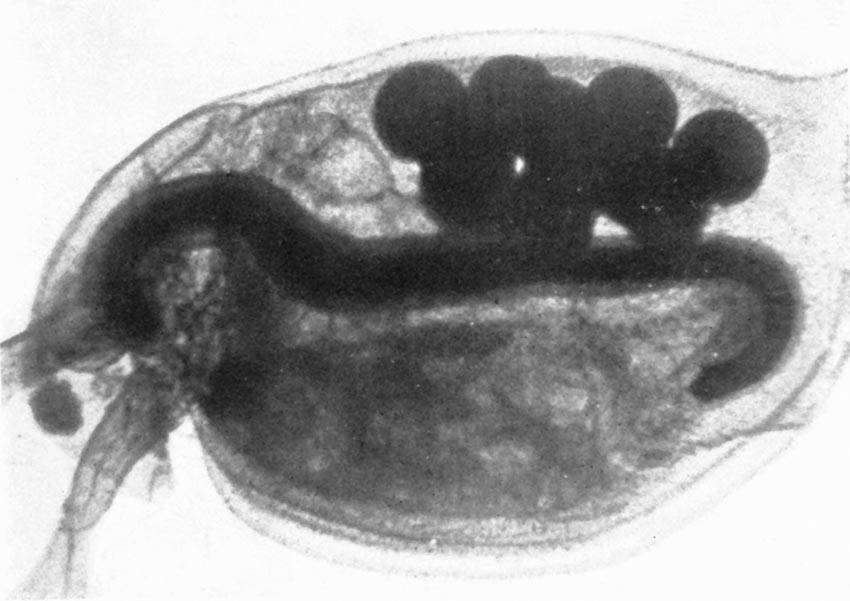

| Moving X-ray Pictures of the Digestion of a Fowl | 149 |

| Stomach and Intestine of a Trout | 152 |

| Digestive Organs of the Frog | 152 |

| Lizard Digesting its Food | 152 |